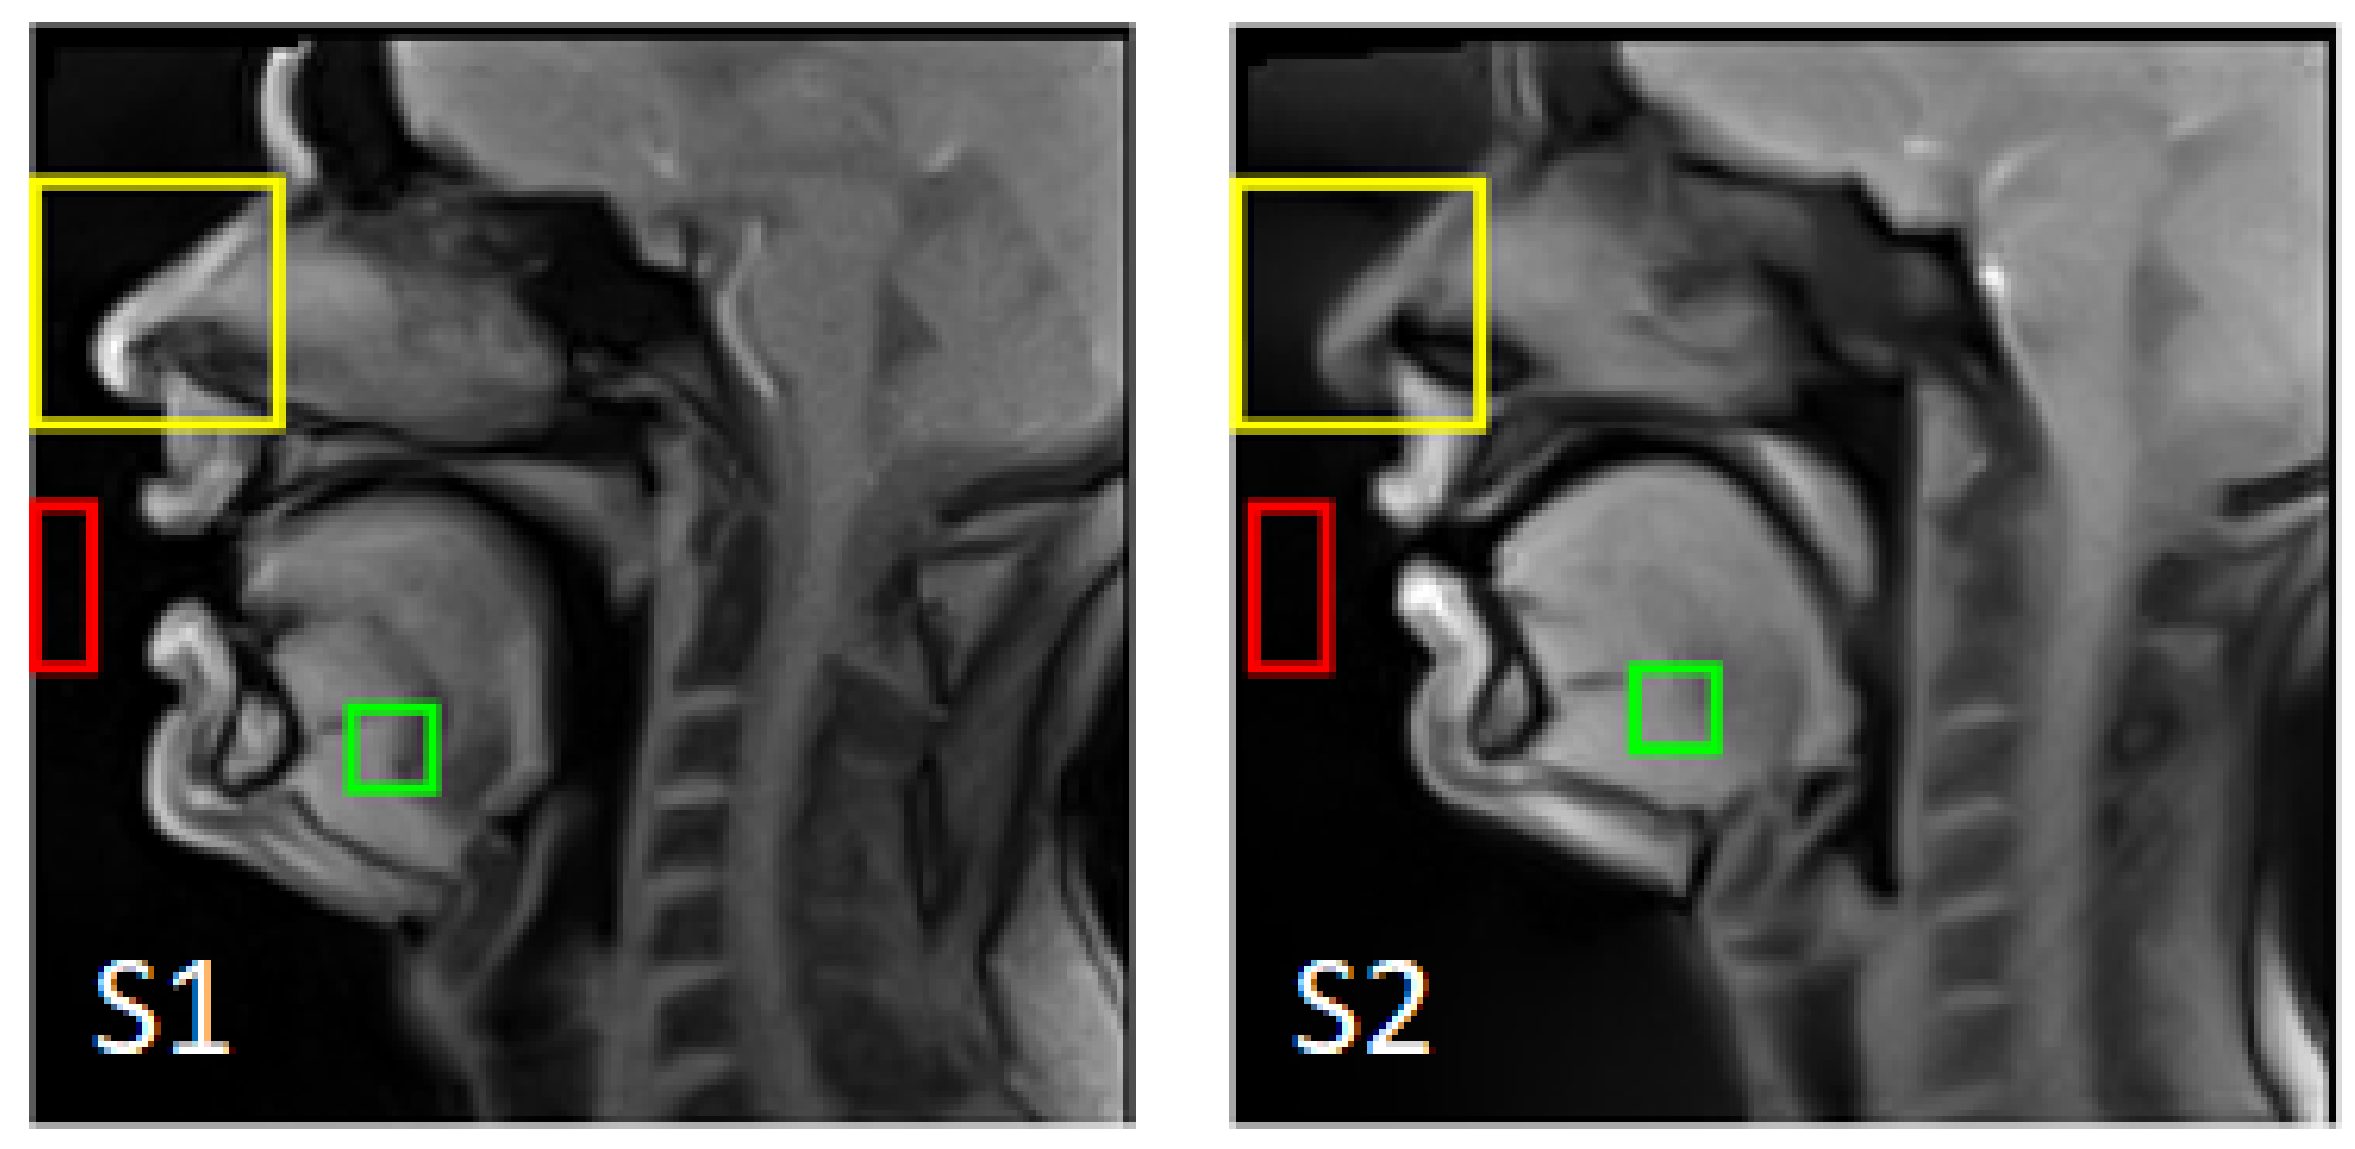

- Rigid registration. Considering the long acquisition time, one can suppose the presence of involuntary head motion. The out-of-plane motion cannot be corrected within the selected multi-slice strategy; however, the in-plane motion can be handled. A region of interest (ROI) including only the subject’s nose (which does not move during speech) was manually selected on the first mid-sagittal image for each subject (see Figure 3). Each lateral slice was registered to the adjacent slice located closer to the center by its translation and rotation: